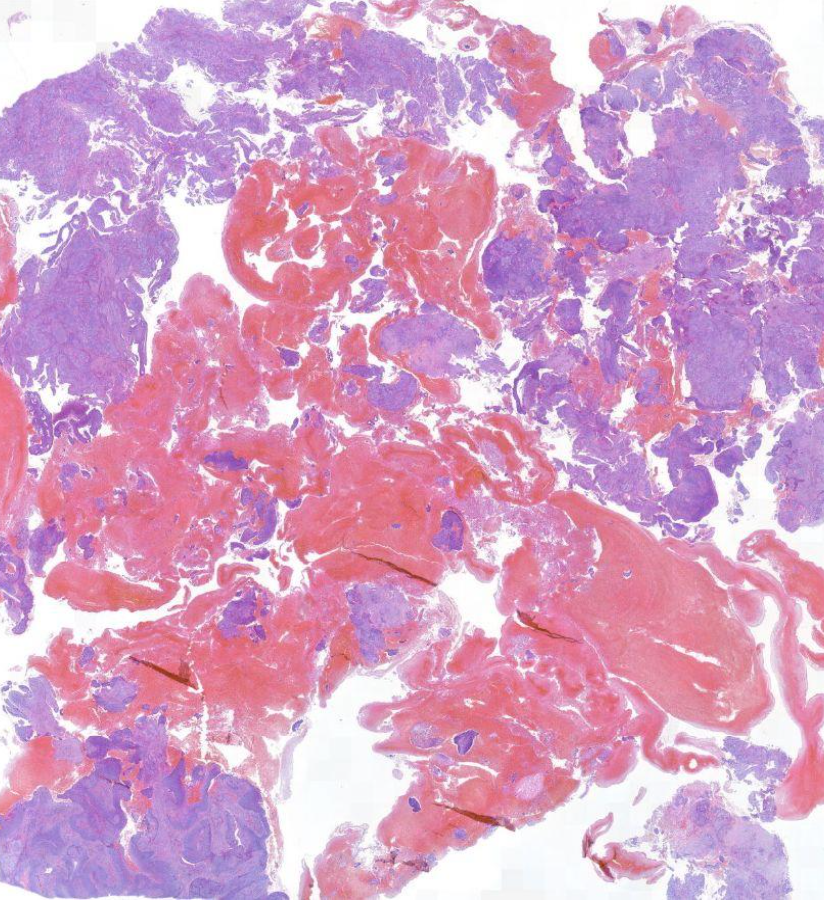

Diagnose?

Pleomorphes Speicheldrüsenadenom = BENIGNE

80% in der Parotis -> nicht destruktiv, nicht invasiv, nur verdrängend

v.a .Parotis, benigne, aufgebaut aus bindegewebiger Kapsel und epithelialen und mesenchymalen Gewebe (v.a. Knorpelgewebe)